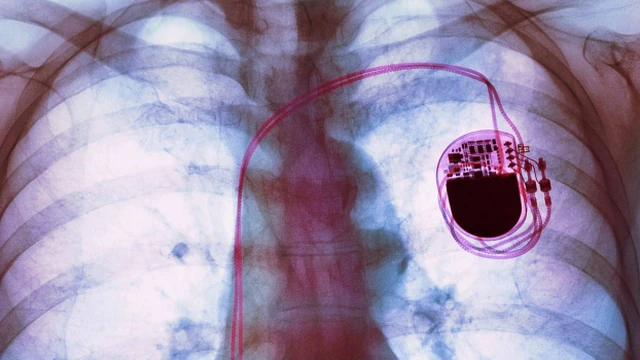

Máy trợ tim, còn được gọi là máy tạo nhịp tim, là thiết bị điện tử mang tính cách mạng được thiết kế để điều chỉnh và kích thích các cơn co thắt tim, đảm bảo nhịp tim và chức năng tối ưu. Trong bài này, chúng ta sẽ đi sâu vào tìm hiểu cơ chế hoạt động của máy trợ tim cũng như những điều cần lưu ý sau khi đặt thiết bị này.

Rối loạn nhịp tim là một trong các tình trạng thường gặp nhất ở tim. Nó gây cảm giác khó chịu và đau đớn cho người bệnh. Để hạn chế các đơn đau ở tim do rối loạn nhịp tim gây ra, máy tạo nhịp tim chính là giải pháp. Vậy máy tạo nhịp tim là gì? Đặt máy tạo nhịp tim có an toàn không? Hãy cùng Nhà thuốc Long Châu tìm hiểu trong bài viết dưới đây nhé!